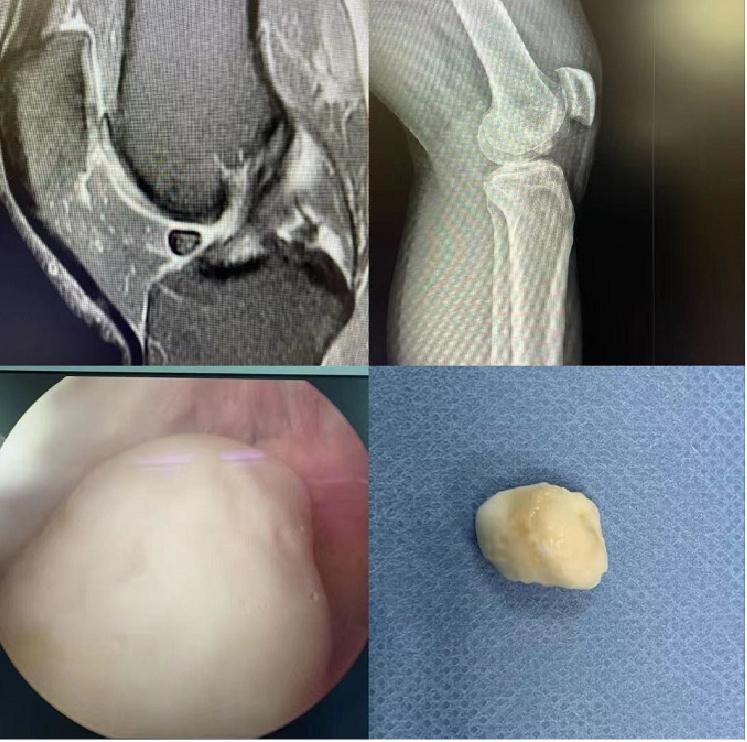

“关节鼠”原来长这样

“关节鼠”并非真正的耗子,而是指关节有退行病变或损伤时,从关节内的组织上脱落下来的组织碎片,因为它们在关节里像老鼠一样游窜,引起关节疼痛、绞锁等症状,故而医学给它们取了一个十分形象的名字——关节鼠。近期,广州中医药大学第三附属医院关节中心收治了一位被“关节鼠”困扰数年的患者张先生。

张先生找到了关节中心关节科主任医师柴生颋,通过详细的体格检查,结合膝关节磁共振,发现罪魁祸首原来就是在长期剧烈运动的情况下,左膝关节不断撞击,关节软骨破坏、剥脱后形成的游离体,最终形成了“关节鼠”,要想彻底改善症状,就要进行关节镜手术,将膝关节中产生的游离体取出。

手术取出游离体的第二天,张先生发现无法伸直的膝关节能够自由屈伸了,没有了那种术前卡顿的感觉了。经过一段时间的系统的康复训练,张先生的膝关节将恢复得更好。

近年来,逐渐普及的关节镜技术,是侦查这些“关节鼠”的能手。属于内窥镜的一种,检查时,在麻醉状态下,作一个极小的切口,插入关节腔内,多方位搜索观察,可以侦查其踪迹,又可以同时进行治疗,对于关节腔内的滑膜炎、骨质增生、软骨损伤、半月板损伤,都可以一并处理并冲洗干净关节腔,延缓出现关节炎的时机,查治结合,一举两得。不过对于过于硕大的“关节鼠”,还需要传统的手术刀来摘取。